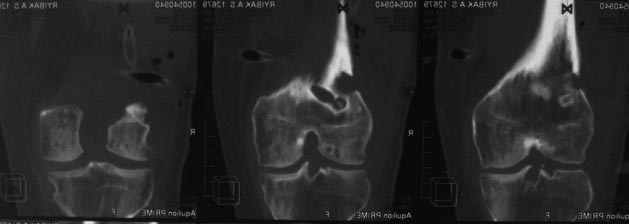

КТ после операции.

Есть остеопороз, но явного остеомиелита не наблюдается.